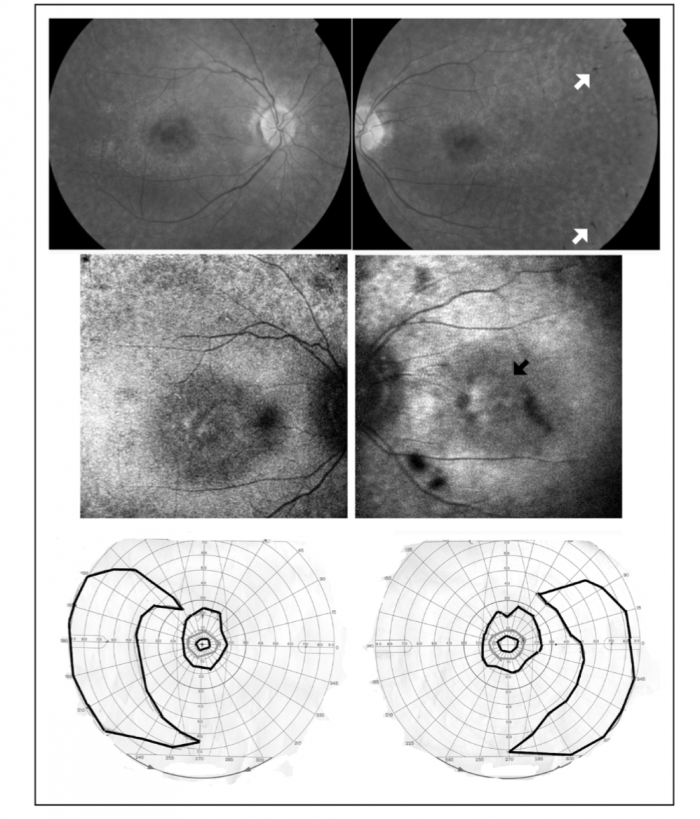

Ophthalmoscopic examination: to identify signs of retinitis pigmentosa.[11]

Visual Field Testing: to identify abnormal visual field defects.[11]

- Ophthalmology: Fundoscopy, visual acuity, visual field (Goldmann perimetry), and electroretinography